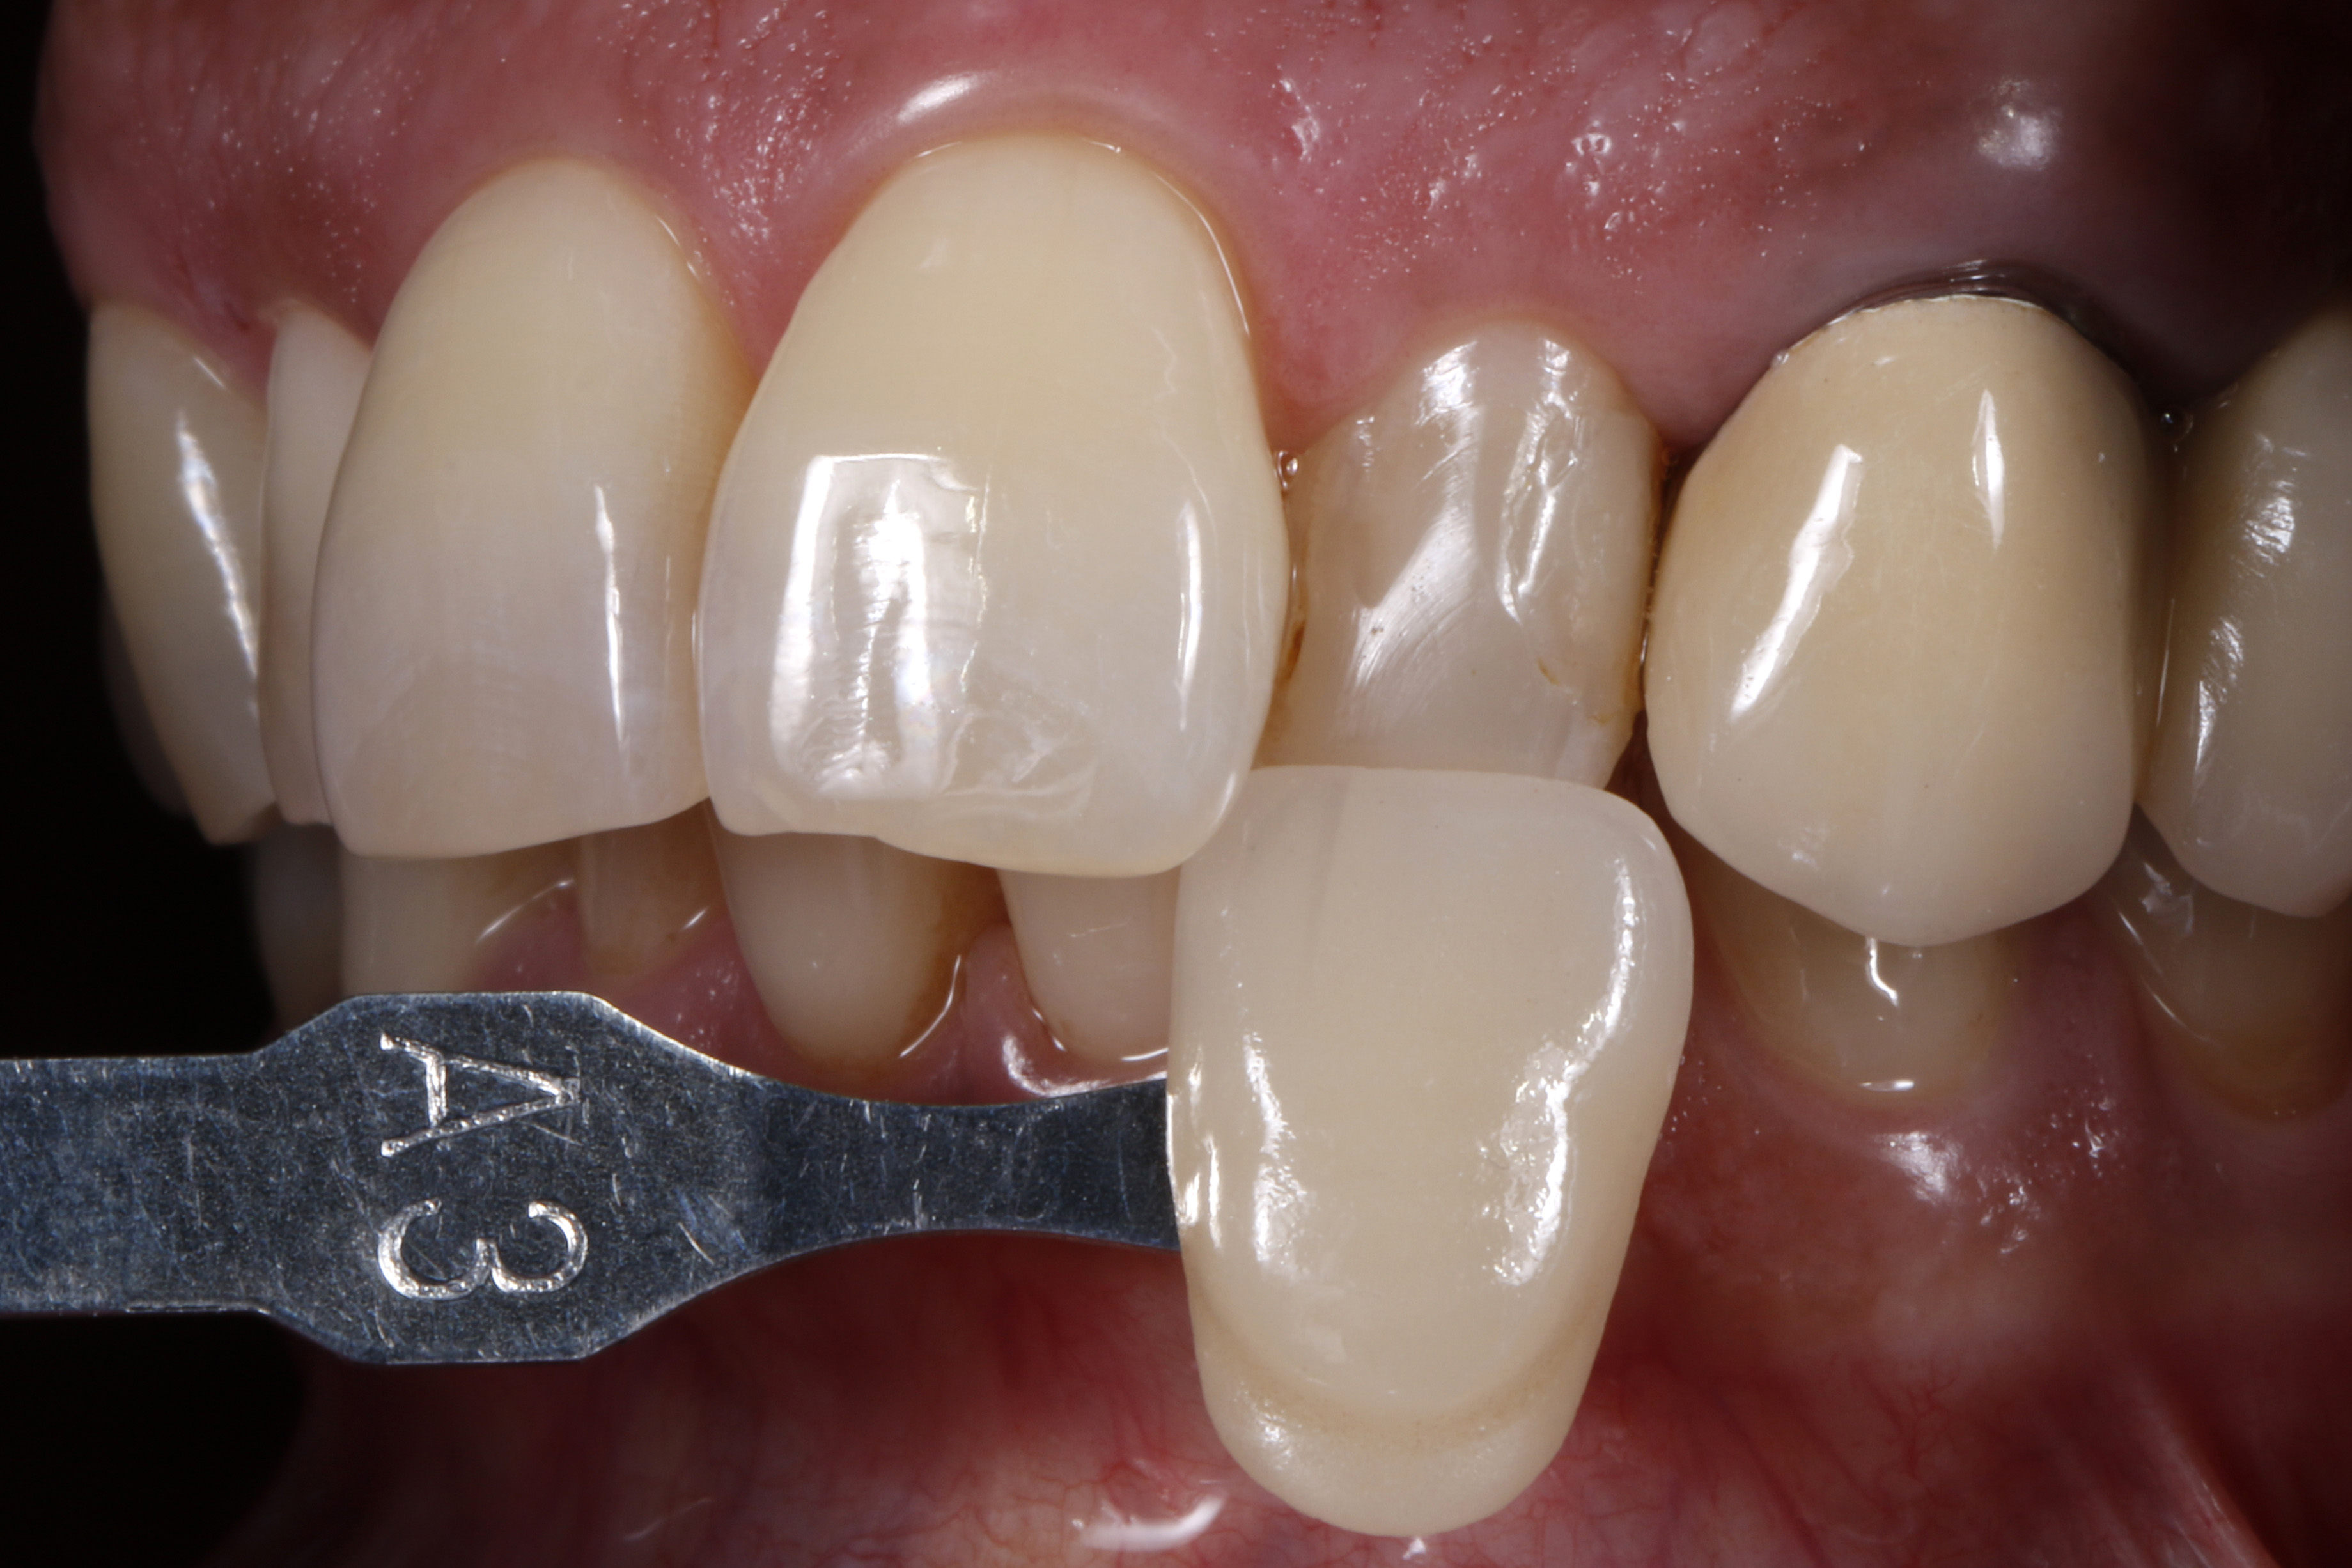

Leczenie rozpoczęto od dokładnego oczyszczenia zęba z zewnętrznych osadów za pomocą pasty profilaktycznej bez fluoru i gumki w kształcie kielicha. Następnie odpowiedni odcień kompozytu określono na wciąż wilgotnym zębie (ryc. 3).

Ryc. 3. Dobór odcienia na wilgotnym zębie

Wybrany odcień kompozytu sprawdzono, nakładając niewielką porcję kompozytu na powierzchnię zęba, który nie został wysuszony i nie był wstępnie zabezpieczony materiałem wiążącym (17). Konieczna jest polimeryzacja próbki kompozytu światłem przez czas określony przez producenta w celu uzyskania miarodajnego porównania optycznego. Dopiero przy wystarczającej ekspozycji na światło fotoinicjator kamforochinon, który jest zawarty w większości kompozytów i ma intensywnie żółty kolor, ulega w dużej mierze zużyciu i przekształceniu w bezbarwny produkt reakcji („fotowybielacz”) (18–23). Po polimeryzacji próbki kompozytu nałożonej na powierzchnię zęba, jej właściwości optyczne porównano z otaczającą zęba substancją pod względem odcienia i stopnia przezierności. Na tym etapie można łatwo dokonać korekty, zastępując niedopasowaną optycznie próbkę materiałem kompozytowym o zoptymalizowanym odcieniu. Ten indywidualny proces weryfikacji, który zajmuje bardzo mało czasu, gwarantuje, że do kolejnej odbudowy zostanie użyty optymalnie dopasowany materiał kompozytowy. Oznacza to, że w niemal wszystkich przypadkach można uniknąć czasochłonnych poprawek, a nawet nowych wypełnień z powodu skarg pacjentów na estetykę.